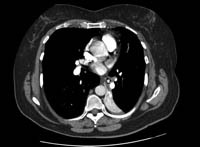

TC de tórax con material de contraste intravenoso, en la que se muestra el colapso total del lóbulo inferior izquierdo, con un objeto radiopaco en el bronquio principal inferior izquierdo, rodeado de un halo de aire

BMJ Case Reports 2008 (doi:10.1136/bcr.06.2008.0013). Copyright 2008 de BMJ Publishing Group Ltd